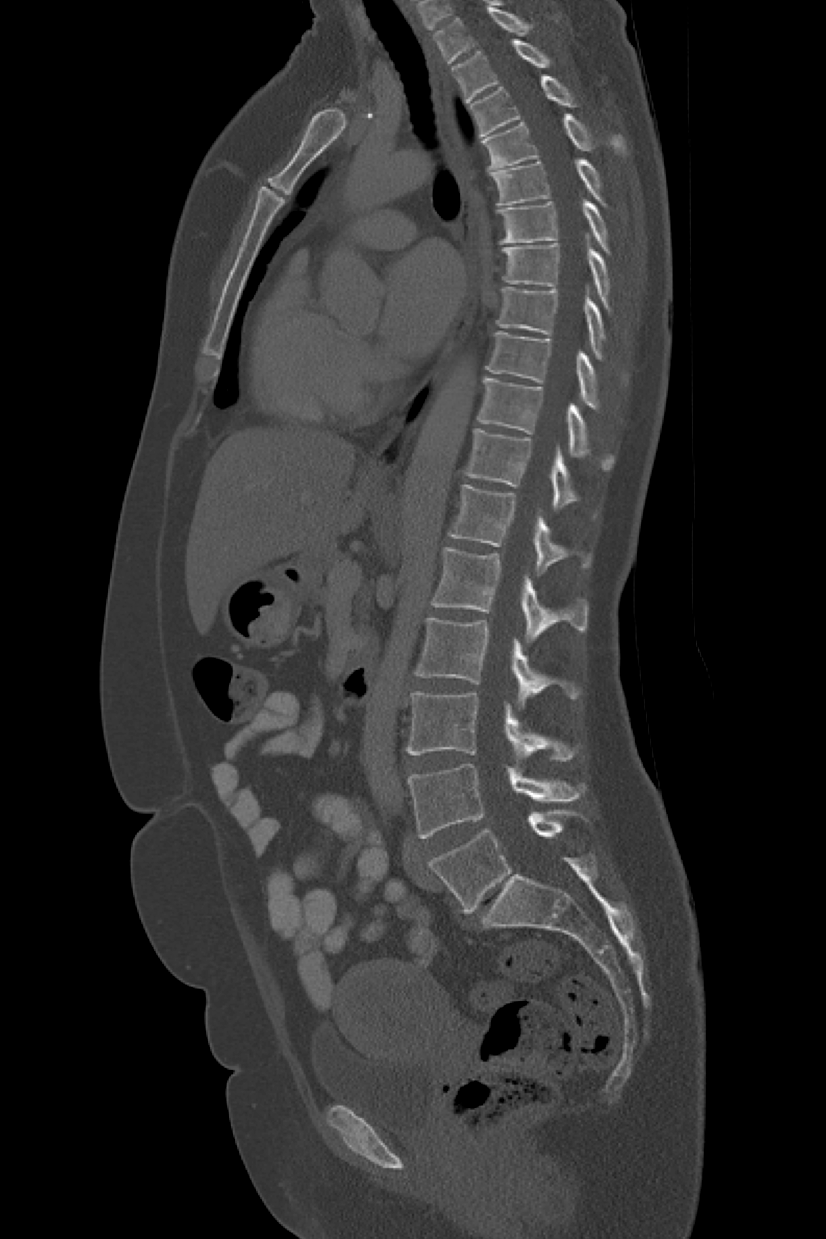

4.2 Vertebral Localization and Segmentation

We evaluated the model on the test sets from the VerSe2019 and VerSe2020 datasets. These test sets contain 113 subjects in total. Each CT volume was pre-processed by smoothing with a Gaussian kernel with σ\sigma = 0.75 mm to reduce noise.

The models have 22.91 million parameters for spine localization, 21.13 million parameters for vertebrae localization, and 17.19 million parameters for vertebrae segmentation. The inference time varies with the field-of-view and the number of visible vertebrae in the CT volume. All experiments were conducted on a dual-socket Intel® Xeon® Platinum 8462Y+ system (64 physical cores, 2.80 GHz, 120 MiB L3 cache) running Linux. On the combined test set of 113 subjects, the average inference time per volume was about 1 min 40 s. Specifically, the process took about 3 s for spine localization, 19 s for vertebrae localization, and 1 min 17 s for vertebrae segmentation. The visualization of vertebral localization and segmentation is shown in Figure 3.

(a) Original CT Image

(b) Segmentation Result

(c) 3D Mesh

Figure 3: Visualization of vertebral localization and segmentation results.